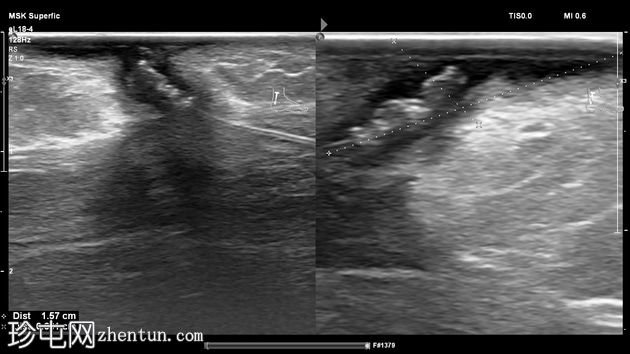

超声检查

2.jpg

纵位

左足跟皮下组织内可见一管状高回声物质,呈串珠状,与手术缝线相符,周围环绕着低回声积液。与缝线相连的是一根细细的、呈轨道状的高回声合成单丝,它穿过跟腱呈弧形走行,该缝线为不可吸收缝线。